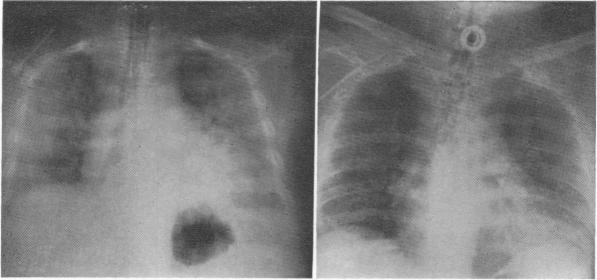

Kellum J M, DeMeester T R, Elkins R C, Zuidema G D

Ann Surg. 1972 May;175(5):657-62. doi: 10.1097/00000658-197205000-00005.